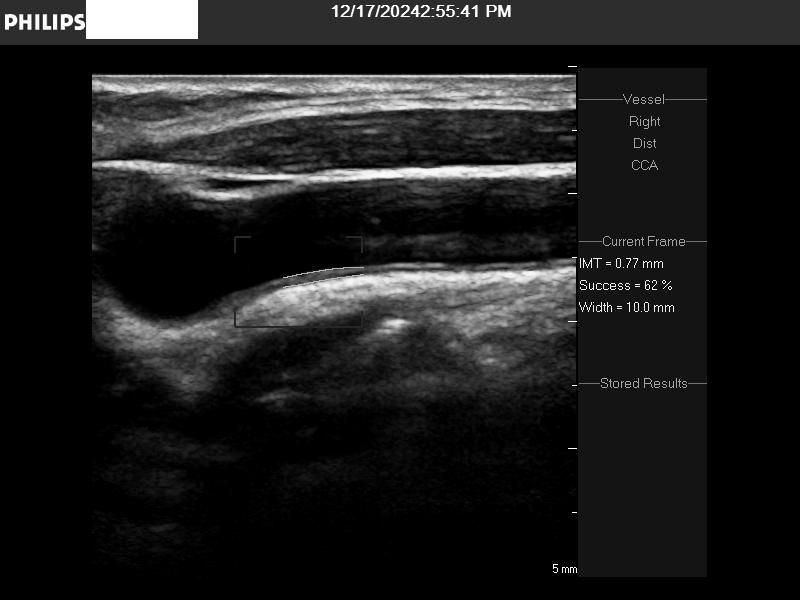

2024년 지난해말 처음으로 경동맥 초음파검사 했는데, 어느정도 수준일까요?

• 3번 째 사진

일반적으로 IMT가 1mm 보다 두꺼운지를 확인하고 혈관에 플라크가 있는지를 봅니다

초음파 사진으로만 보면 동맥경화가 경증으로 있는 것 같습니다